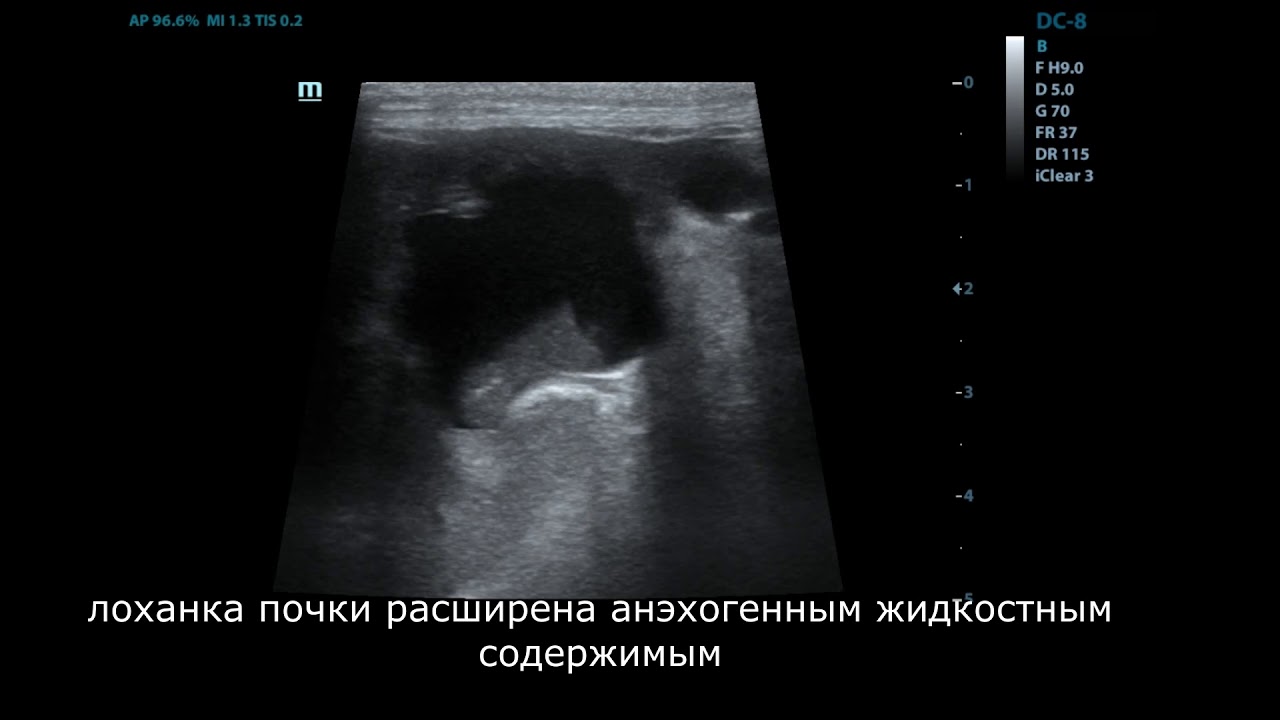

Если не обеспечить своевременный отток мочи, то формируется гидронефроз (наполнение полости почки мочой с последующим формированием атрофии ее тканей). Кроме того, нарушение процессов оттока мочи приводит к развитию пиелонефрита.

Мочеточники имеют форму трубок и соединяют почку с мочевым пузырем. Их основная функция – проводить мочу из лоханки почки в мочевой пузырь, не позволяя ей двигаться в обратном направлении. Лоханка почки – это соединение небольших сосудов почки, в которых и скапливается моча.